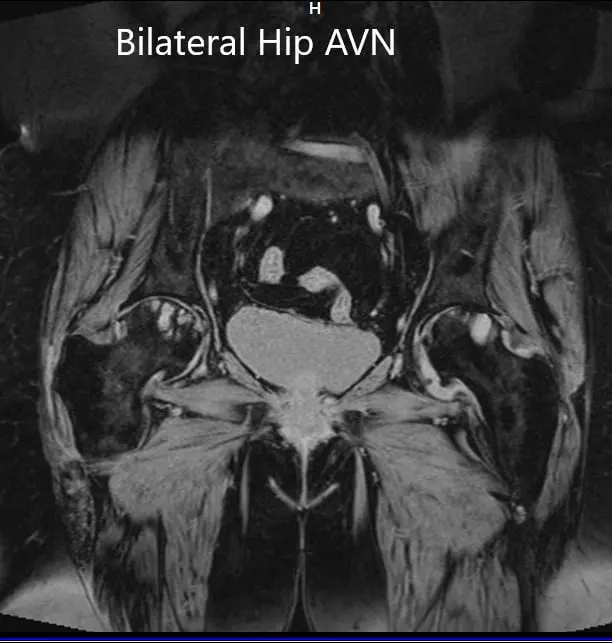

MRI was obtained which showed:

Right Hip Joint: There is a loss of sphericity of right femoral head, involving more than 2/3 of the circumference. In the superior part of the right femoral head, a focal lesion is visualized which is bounded by a serpiginous T1 hypointense margin. The lesion is hypointense on both T1 & T2WI relative to the marrow (Mitchell class – D).

No subchondral fracture is detected. A minimal amount of fluid is seen in the joint cavity. The femoral neck and acetabulum display normal signal intensity. Muscles in view display normal signal intensity.

Left hip joint: Displays similar although less severe changes. The sphericity of the left femoral head is maintained. There is more than 2/3 circumferential involvement of the left femoral head. No subchondral fracture is seen. No joint effusion is seen.

Coronal section of T2WI and T1WI of pelvis MRI.